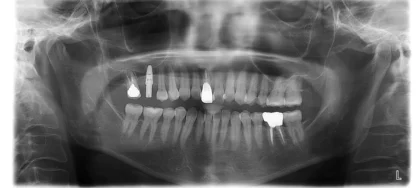

こちらの患者様のお口の状態はインプラントを支える骨がしっかりしている、上顎洞まで十分な距離があり、歯周病のリスクも低いことを詳しく説明しました。